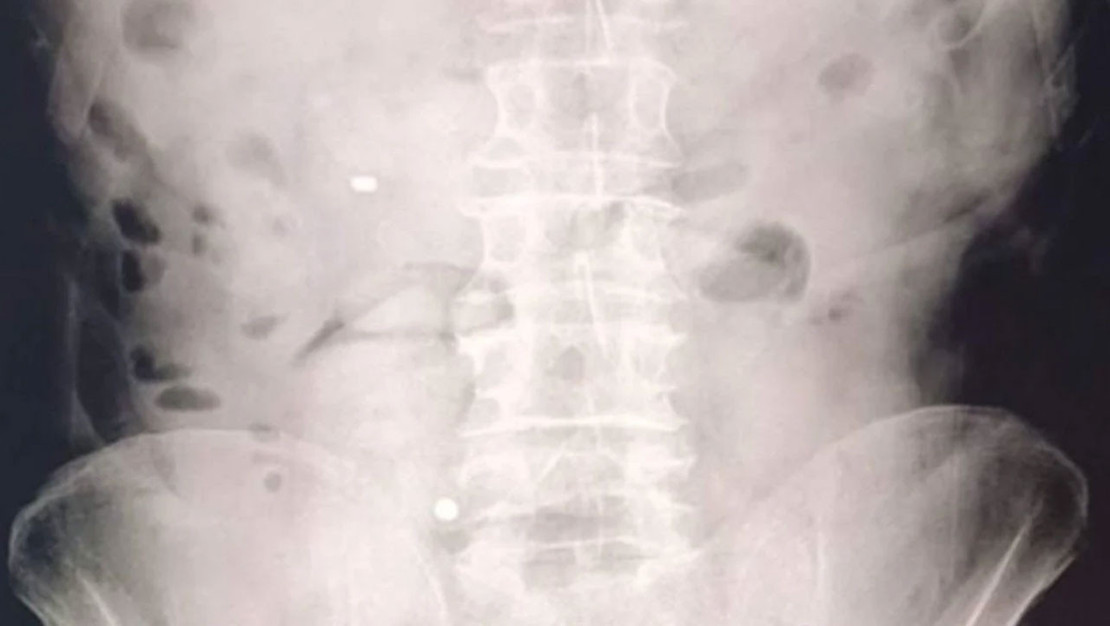

MİDE VE BAĞIRSAKTA UYUŞTURUCU BULUNDU

Gözaltına alınan şüphelilerin hastanede yapılan kontrolleri ve çekilen röntgen filmleri sonucunda mide ve bağırsaklarında çok sayıda uyuşturucu madde içeren kapsül bulunduğu belirlendi. Şüpheliler, hastanede kontrollü gözetim altında tutulurken, tıbbi müdahaleler sonucunda toplamda 93 parça halinde 1 kilo 70 gram metamfetamin ele geçirildi.